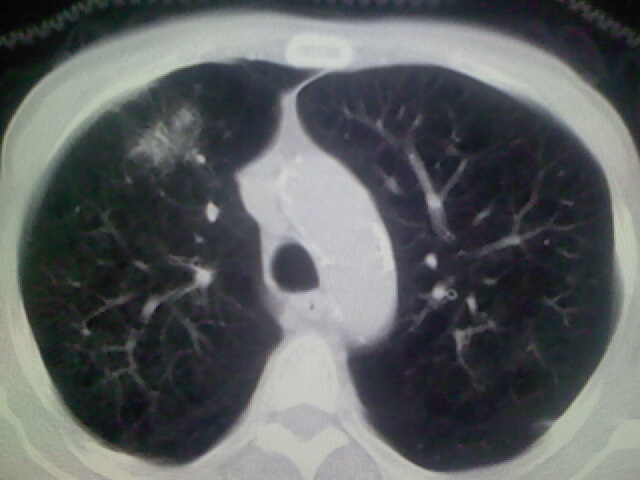

男,70y,胃占位,重度贫血,黑便3月余,伴恶心,纳差,乏力

肺内考虑原发(周围型肺癌)

右上肺周围型肺癌,肝内多发低密度影---转移瘤?建议增强;胃壁明显增厚.

1)考虑右肺上叶周围型肺癌并纵隔及右颈部淋巴结转移,肝脏多发性转移。2)肺气肿。3)冠状动脉及主动脉钙化。

支持右肺上叶周围型肺癌伴肝内多发转移.胃建议充盈后重扫描.慢性支气管炎伴肺气肿.